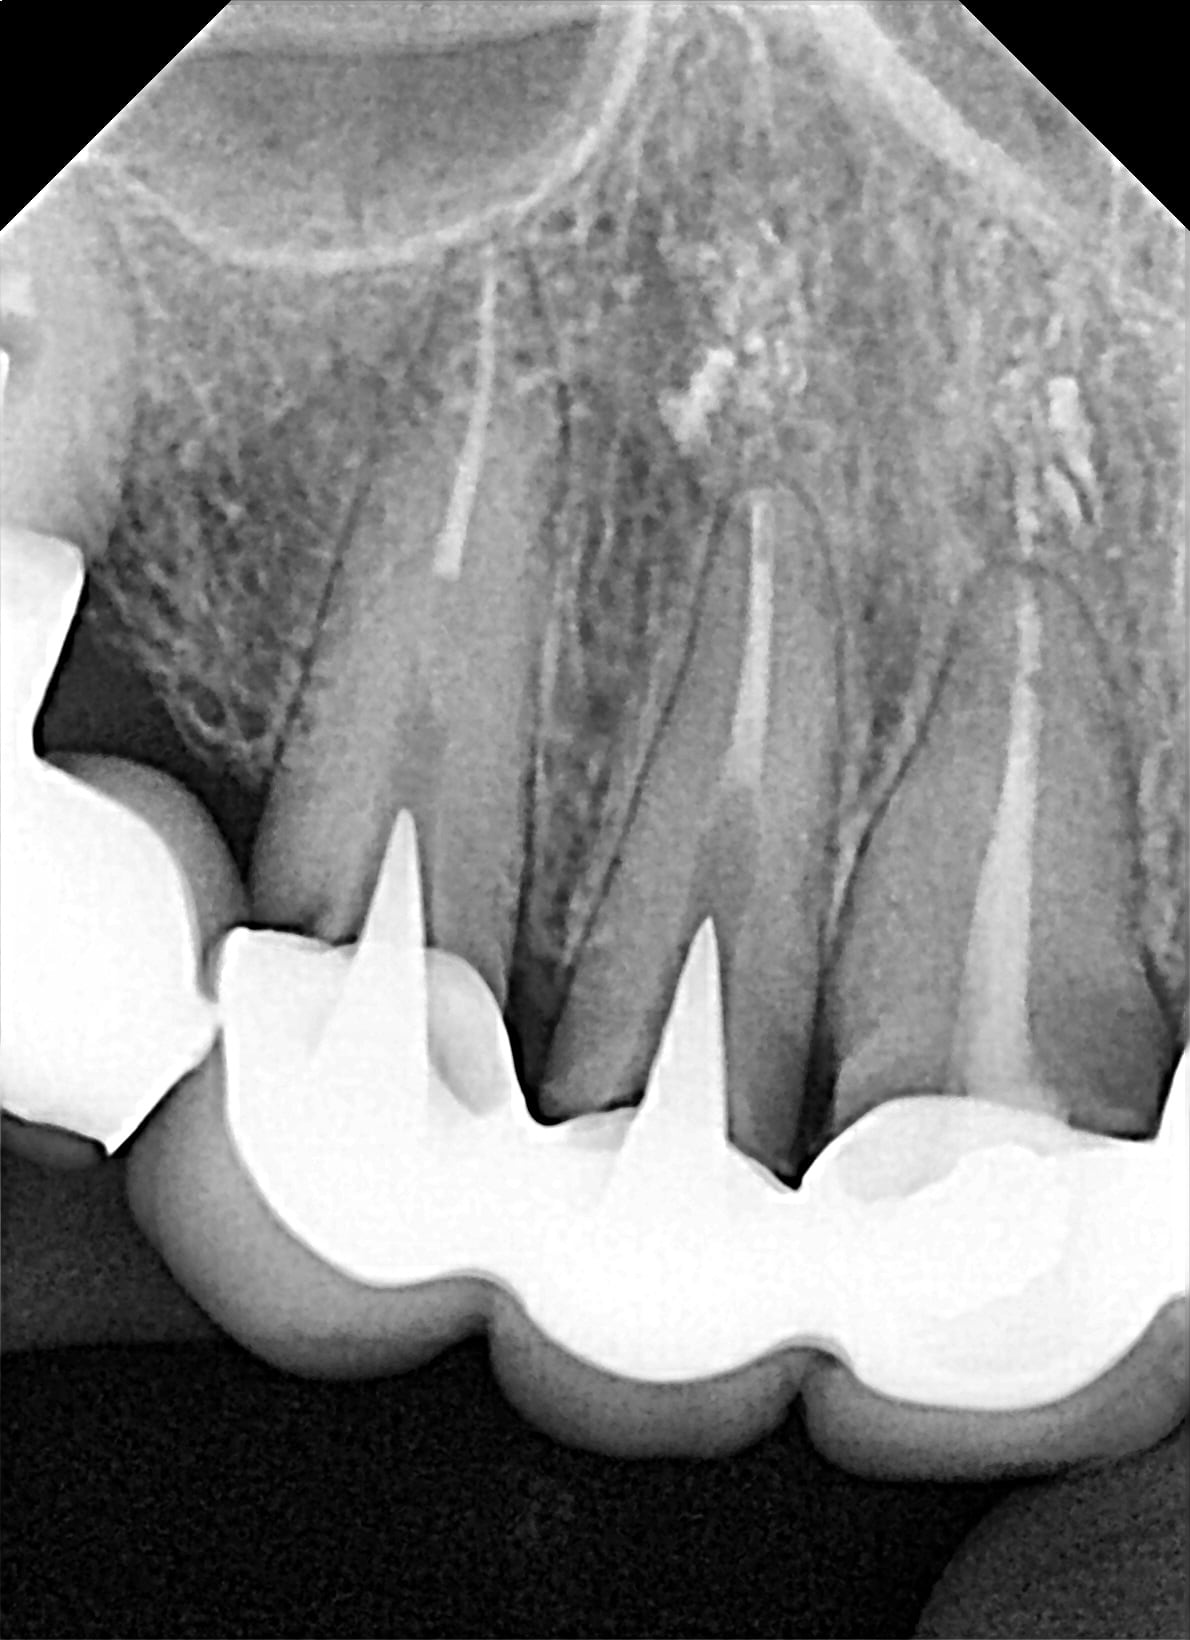

celui là a été posé il y a 6 mois. le praticien a pas du avoir de mal à l'enfiler, J'ai pas de mal a démonter, le patient non plus ^^

12 vhvwh2 - Eugenol